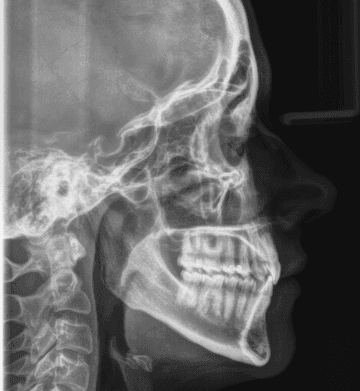

X-RAYS